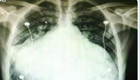

男子心臟如足球大 被取"瘦身"